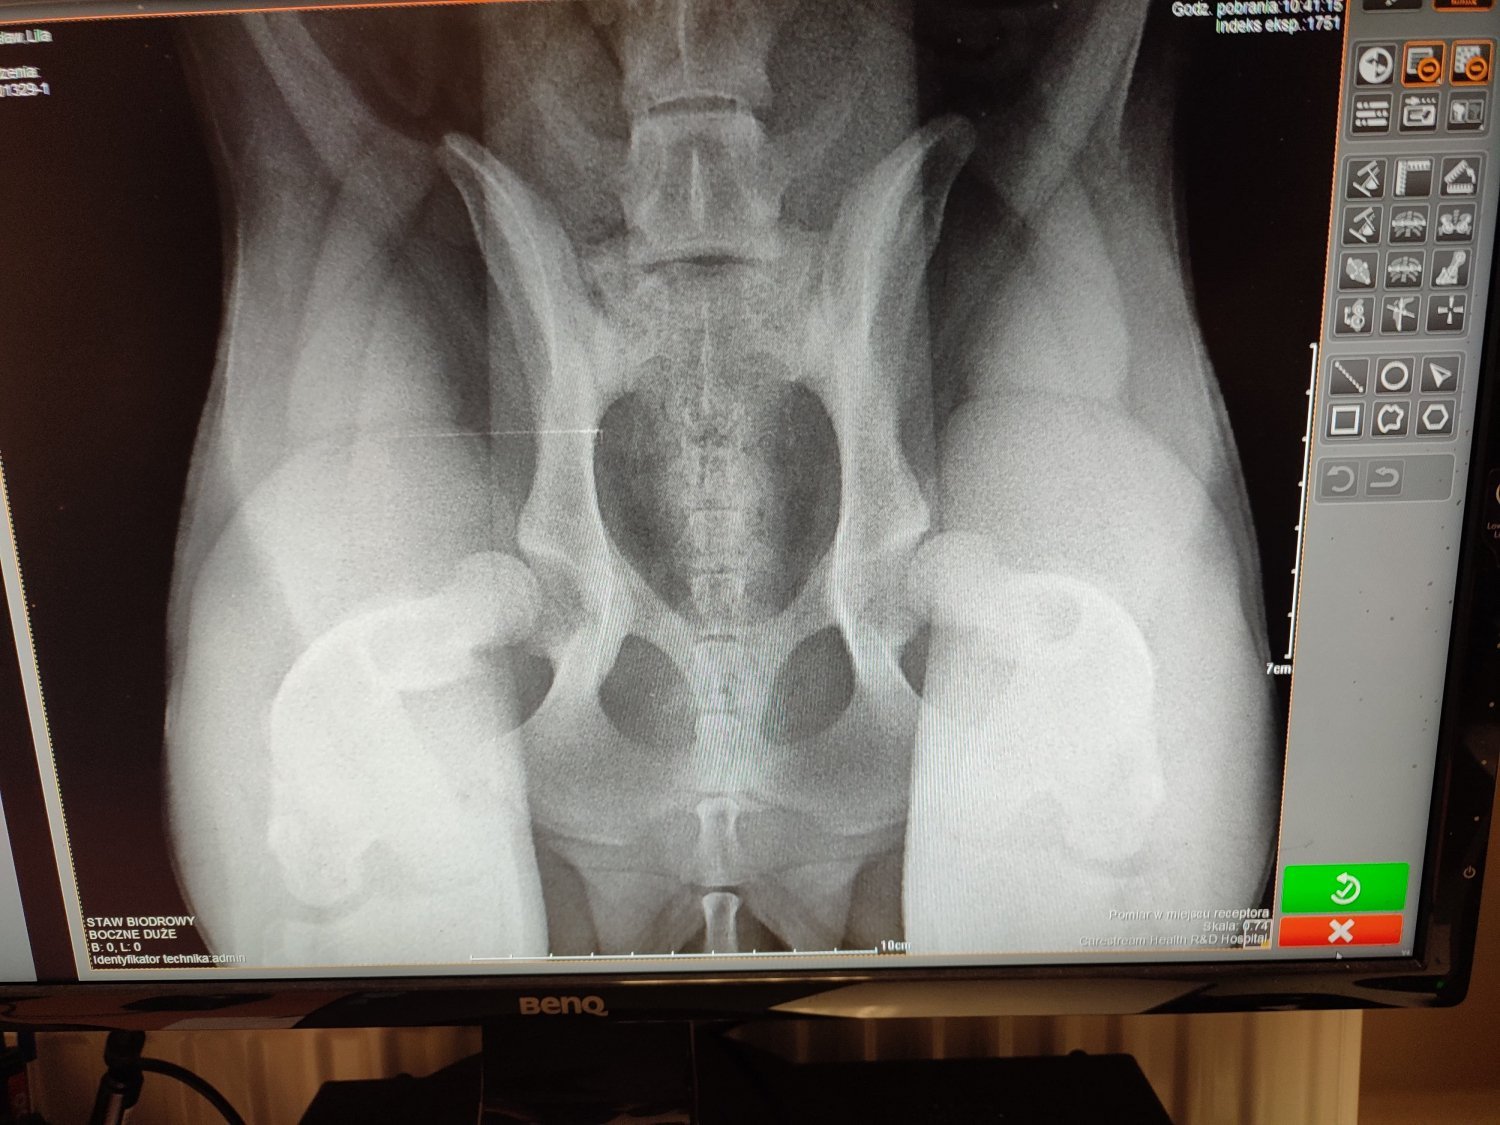

Zrzutki ciąg dalszy, na operację drugiego stawu. Ten staw jest lepszym stawem, ale i on zdiagnozowany jest jako zaawansowana dysplazja. Na tą chwilę Lila ma się dobrze, czasami pomarudzi z nudów bo musimy ją trzymać odizolowaną, żeby ograniczyć jej ruch do minimum, ale humor jej dopisuje kiedy się powymiziamy. Na szczęście pracuje z domu i biuro przeniosłem do tego samego pokoju. 2 operacja będzie taka sama jak pierwsza, czyli darthoplastyka, przeszczep kości. Na jej starym stawie już widać poprawę, nie "słychać" kości jak chodzi, rana po operacji dobrze się zagaja. Niestety ten miesiąc jest miesiącem bardzo chudym, bo przez operację wypłukaliśmy się do zera, dlatego nie zamykam zrzutki i mam nadzieję na drobne chociaż wsparcie. Bardzo wam wszystkim dziękuję za dotychczasowe wpłaty, bez nich nie bylibyśmy w stanie nawet zacząć tej podróży ku zdrowiu naszego kochanego psiaczka

Cześć, zrobiłem zrzutkę ponieważ sam sobie z tym nie poradzę. Mam małego-dużego szczeniaczka, kochaną Lilę która ma 8 miesięcy i 30kg. Strasznie szybko rosła przez ostatnie miesiące co spowodowało że rozwinęła się u niej zaawansowana dysplazja biodrowa. To było coś czego się spodziewałem, w końcu to mieszanka labradora z owczarkiem niemieckim, natomiast nigdy nie wyobrażałem sobie, że będzie tak źle, że skończy się to operacją. Główki kości udowej nie wchodzą w panewkę miednicy, co powoduje ścieranie się chrząstki, ból i kicanie podczas biegania. Lila to bardzo kochany piesek, zabrałem ją jako szczeniaczka od pewnej sąsiedzkiej wpadki. Chciałem dać jej dom, schronienie i miłość, teraz chciałbym móc również zadbać o jej zdrowie. Czekają ją 2 operacje, jedna to DPO, podwójne cięcie miednicy, jej miednica zostanie "złamana" w pół, żeby nałożyć tą miednicę, aby główka wchodziła w panewkę. To na pewno pomoże na jej lepszy, lewy staw. To właśnie na tą operację zbieram. Kolejna, która kosztuje kolejne 4000 do dartoplastyka. Tą zapłacę samemu, jeżeli uda mi się dostać kredyt. Polega ona na przeszczepie kości, aby prawy staw nie wypadał, a miał więcej miejsca do podparcia. Z tego co rozumiem, dopiero po tych dwóch operacjach jej gorszy staw w końcu będzie się do czegoś nadawał. Do biegania wśród psiaków, do ganiania za patykami, do radosnego i bezbolesnego dzieciństwa. Za każdą, nawet najmniejszą wpłatę będę bardzo wdzięczny,